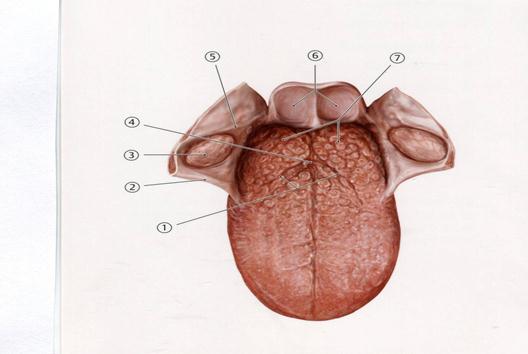

А. Алдыңғы милық

А. Таңдай бадамша безі

В. Тіл бадамша безі

С. Таңдай- тілдік доға

+D. Таңдай – жұтқыншақтық доға

Е. Шекаралық жүлге